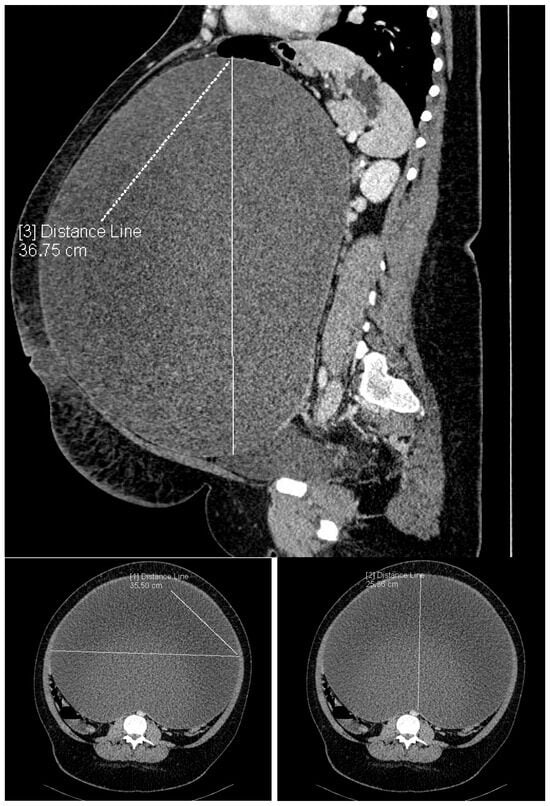

2. Detailed Case Descriptions